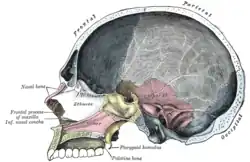

Secção sagital do crânio

Secção sagital do crânio -